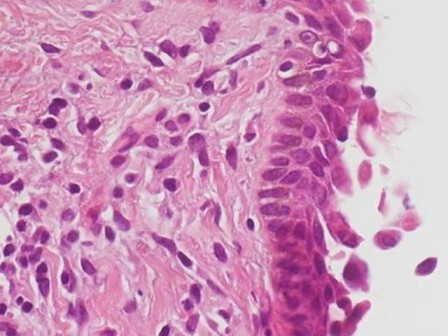

膿汁のグラム染色ではclusterを形成するグラム陽性球菌を多数認め、また翌日には血液培養が陽性になり黄色ブドウ球菌(メチリシン耐性黄色ブドウ球菌:MRSA)と同定されたため、ステロイドは中止した。そして皮膚生検の病理所見では、「表皮は角層と顆粒層を欠いており、表層では棘融解した角化細胞が散見される(図4)」という結果であり、SJS/TENではなく、SSSSと診断された。

図4 表層では棘融解した角化細胞が散見される